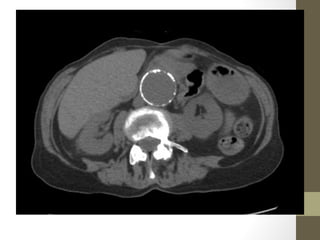

Kidney Stones- CT

Style

Hydronephrosis

Renal Calculus

Hydro-ureter

UVJ Stone

Radiology- CT Scan •Detect leaking AAA (in stable patient) • Evaluate for renal calculi, appendicitis, perforation (free air), diverticulitis, abscess, mesenteric ischemia, masses, obstruction • Sensitivity and specificity vary • Not a place for unstable patients • Contrast • PO and IV contrast in most patients • sometimes rectal contrast is helpful to look for large bowel problems (appendicitis) • In patients with renal insufficiency • give IV contrast judiciously in patients • consider ultrasound as an alternative if possible • a creatinine > 1.5 usually requires bicarbonate and fluid hydration to minimize contrast nephropathy

Rapid Case #18 •28 yo post-partum healthy female • Acute R flank pain radiating to groin • Exam: Abd soft, non-tender without CVA tenderness • UA with 2+ RBC, no WBCs • CT with R Ureteral Calculi • Dx: Renal Colic

• 86.

• 87.

• 88.

• 89.